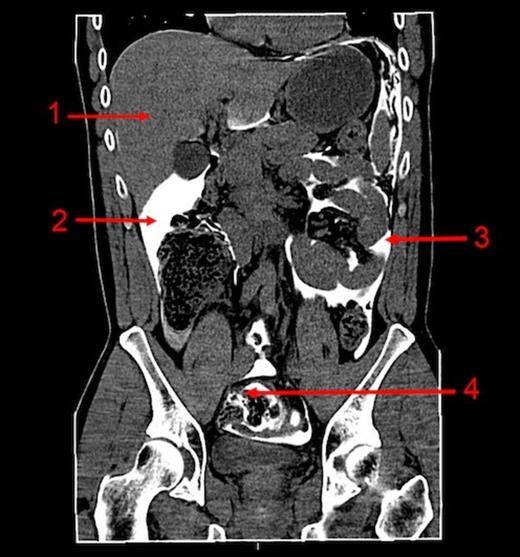

A 42-year-old HIV-infected man presented himself to our emergency department with severe abdominal pain five hours following anal fisting. Clinical examination showed an agitated male with no tachycardia, hypotension or fever. Physical examination of his abdomen revealed tenderness of the complete abdomen with signs of peritonism. A plain abdominal radiograph was reported to have normal findings. Laboratory results showed no abnormalities. Based on his clinical condition, a CT-scan with rectal contrast of the abdomen was performed. The CT-scan showed a perforation of the sigmoid 40 cm above the anus.Figure 1 shows rectal contrast throughout the complete abdomen as high as the diaphragm.

CT abdomen (coronal) with rectal contrast:1. Liver, 2. Contrast in the sub hepatic region, 3. Contrast in the left abdomen, 4. Sigmoid with extra luminal contrast